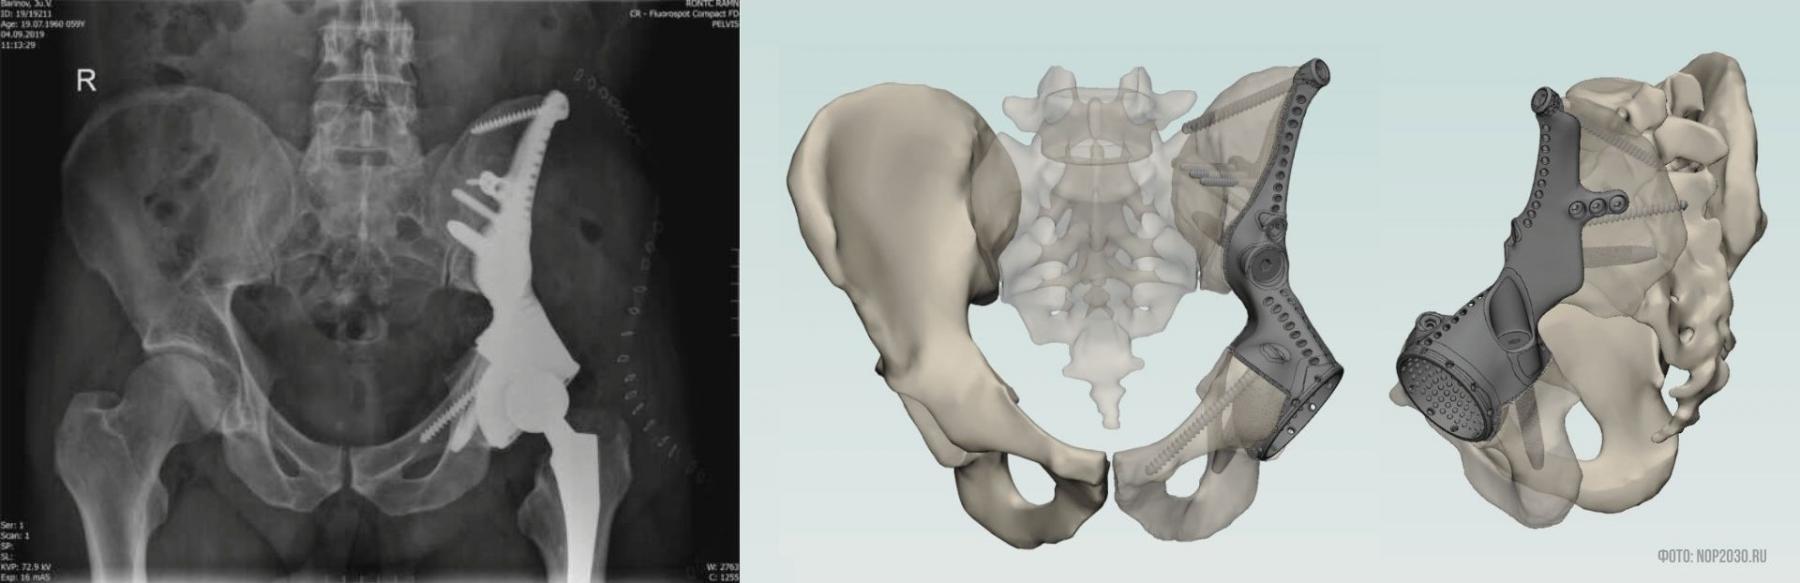

Эндопротезирование 3D-имплантами

Еще недавно после удаления пораженных опухолью костей сложных анатомических локализаций (таких как таз, грудная стенка, локтевой и лучезапястные суставы) пациентам не выполнялась реконструкция удаленных фрагментов кости, что сказывалось на функциональном результате (сохранении и восстановлении опорно-двигательных функций) и приводило к инвалидизации больного.

Ситуация изменилась после появления 3D-принтеров, которые способны распечатывать изделия из титана (материала, разрешенного для имплантации в тело человека).

Подготовка к такой операции начинается с компьютерной томографии, позволяющей определить точные размеры опухоли. Затем выполняется 3D-модель предполагаемого дефекта, и на ее основании определяются границы резекции. Зная их, биоинженеры (специалисты, которые сочетают в себе инженерные навыки со знаниями медицины и анатомии) изготавливают индивидуальный 3D-имплант.

Вмешательство сначала выполняется на виртуальной модели (чтобы правильно подобрать протез), и только затем проводится операция. Хирургу важно не только установить протез, но и сохранить мышечную архитектонику (которая обеспечивает работоспособность мышц). Только в таком случае протез прослужит несколько десятилетий и не потребует замены, а пациент вернется к привычной жизни, забыв о своем заболевании.